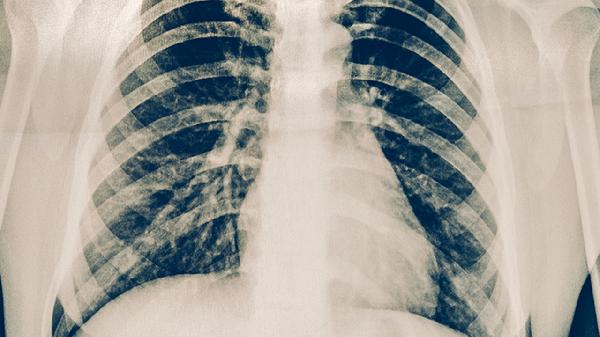

肋骨骨折如何恢复 肋骨骨折的康复训练方法告诉你

康复期间需保持每日蛋白质摄入不少于1.2g/kg体重,多食用牛奶、鱼肉等富含钙磷的食物。6周内避免高尔夫等扭转胸廓的运动,睡眠时使用多个枕头维持30度卧位。定期复查X线观察骨痂形成情况,若出现持续胸痛、呼吸困难需立即就诊。戒烟可显著降低并发症风险,冬季注意保暖预防呼吸道感染。